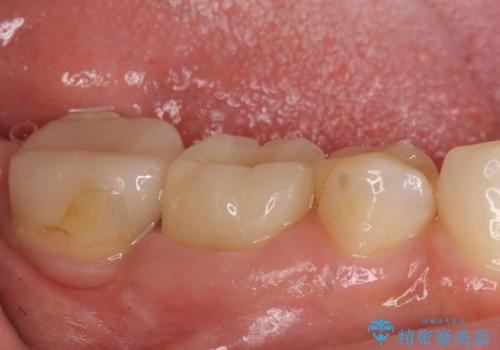

- たまに疼くことがあると他院を受診したところ抜歯を勧められたが、歯を残せないものかと当院にいらっしゃった方の症例です。

診査の結果抜歯の必要性はなさそうだったため再根管治療を行い、その後オールセラミッククラウンによる補綴を行いました。

今回用いたオールセラミッククラウンはジルコニアフレームという白い素材の上にセラミックを盛っているため、審美性が非常に高いのが特徴です。

また、ジルコニアは人工ダイヤモンドの材料にも使われているほど高い強度を持っており、そのためオールセラミッククラウンは審美性だけでなく、奥歯やブリッジの補綴も可能とするクラウンです。